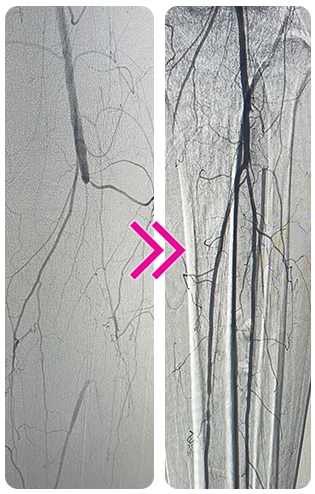

Removal of Multifocal Organized Thrombi Using the Pounce™ and Pounce™ LP Thrombectomy Systems

Michael Nagib, MD

A female patient in her mid 70s presented with a 1-day history of left lower extremity pain. The patient reported pain in her left calf and foot that worsened with activity. Patient history included gastric cancer and atrial fibrillation, with cessation of anticoagulation due to upcoming gastrointestinal endoscopy. On physical exam, palpable pulses were found in the right foot and diminished pulses were found in the left foot, the latter intermittently detected via Doppler ultrasound. Motor function and sensation were intact bilaterally, but a temperature difference was observed between the left and the right foot.